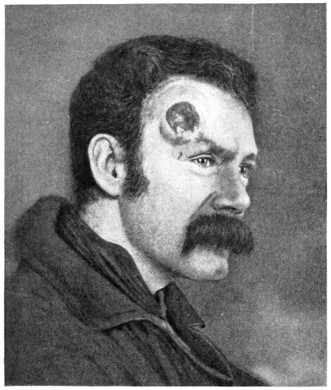

Fig. 20. An Occipital Cephalocele. (For further description, see text.)

1. Occipital cephaloceles—the commonest variety—occupy, anatomically, two positions (1) between the two lower segments of the occipital bone (inferior occipital cephaloceles), often involving the foramen magnum and sometimes complicated by a condition of cervical spina bifida, and (2) between the two upper segments of the occipital bone (superior occipital cephaloceles), occasionally involving the posterior fontanelle.

The tumour may possess a broad base or may be definitely pedunculated. In the former instance the gap in the bone may be of considerable size and the margins everted: in the latter case, the hole may be quite small.

The deformity is frequently associated with other congenital defects—hydrocephalus, microcephalus, spina bifida, hare lip, hernia, and talipes.

Sincipital cephaloceles are usually quite small, but the occipital variety and those situated in[35] the region of the anterior fontanelle frequently attain a great size (see Figs. 20-22).

Fig. 22. An Occipital Cephalocele. (For further description, see text.)

The following case serves to illustrate some of these facts:[9]—

The child was 3 months old, and presented a tumour, the size of an orange, situated between the occipital protuberance and the nape of the neck. The mass was pedunculated, the stalk being about the size of a four-shilling piece in diameter. It was soft, translucent, irreducible, and swelled up on coughing. An attempt at removal was carried out, and, after incising the outermost layers, three ounces of cerebro-spinal fluid escaped. A second tumour was then found occupying the base of the swelling. This was also punctured, more fluid escaping. Both sacs were cut away and the wound sewn up. Death occurred on the third day, preceded by convulsions, retraction of the head and neck, and high fever. The autopsy showed that the fontanelles were widely open, the anterior measuring 4 inches from side to side and 21⁄2 from before backwards. The bones of the vault were markedly thinned. In the subdural space there was a quantity of fluid, and the cerebral substance was soft and diffluent, the convolutions flattened, and the ventricles distended. There was a broad gap in the occipital bone, extending downwards into the foramen magnum, and in this situation the cerebellum had bulged backwards into the protruding mass. (See Fig. 22).